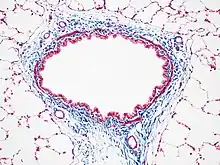

Masson's trichrome is a three-colour staining procedure used in histology. The recipes evolved from Claude L. Pierre Masson's (1880–1959) original formulation have different specific applications, but all are suited for distinguishing cells from surrounding connective tissue.

Most recipes produce red keratin and muscle fibers, blue or green collagen and bone, light red or pink cytoplasm, and dark brown to black cell nuclei.

Another common variant is the Masson trichrome & Verhoeff stain, which combines the Masson trichrome stain and Verhoeff's stain.[2] This combination is useful for the examination of blood vessels; the Verhoeff stain highlights elastin (black) and allows one to easily differentiate small arteries (which typically have at least two elastic laminae) and veins (which have one elastic lamina).